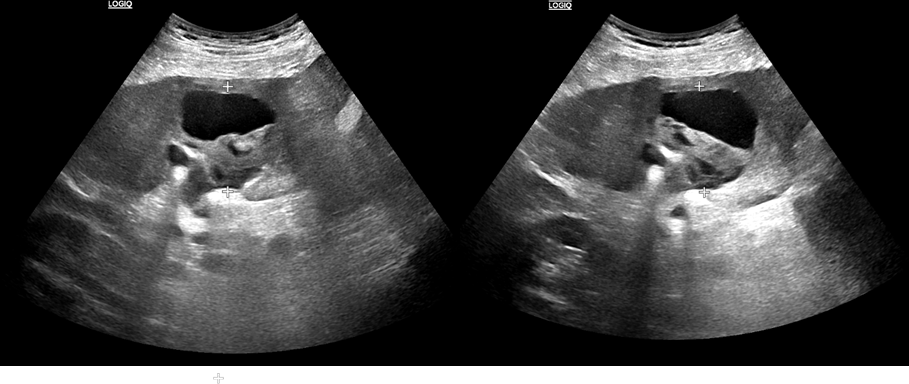

HALLAZGOS RADIOLÓGICOS